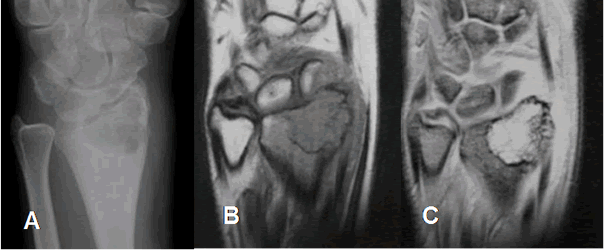

Fig 84. Condroblastoma.

A: Rx AP, B: RM coronal en T1 y C: RM coronal en GE. Lesión lítica en el radio distal, de crecimiento expansivo, pero sin ruptura de la cortical, ni masa de tejidos blandos, por condroblastoma.